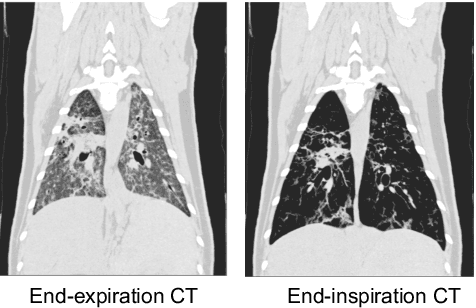

Abstract:Chest computed tomography (CT) at inspiration is often complemented by an expiratory CT for identifying peripheral airways disease in the form of air trapping. Additionally, co-registered inspiratory-expiratory volumes are used to derive several clinically relevant measures of local lung function. Acquiring CT at different volumes, however, increases radiation dosage, acquisition time, and may not be achievable due to various complications, limiting the utility of registration-based measures, To address this, we propose Lung2Lung - a style-based generative adversarial approach for translating CT images from end-inspiratory to end-expiratory volume. Lung2Lung addresses several limitations of the traditional generative models including slicewise discontinuities, limited size of generated volumes, and their inability to model neural style at a volumetric level. We introduce multiview perceptual similarity (MEAL) to capture neural styles in 3D. To incorporate global information into the training process and refine the output of our model, we also propose self-ensembling (SE). Lung2Lung, with MEAL and SE, is able to generate large 3D volumes of size 320 x 320 x 320 that are validated using a diverse cohort of 1500 subjects with varying disease severity. The model shows superior performance against several state-of-the-art 2D and 3D generative models with a peak-signal-to-noise ratio of 24.53 dB and structural similarity of 0.904. Clinical validation shows that the synthetic volumes can be used to reliably extract several clinical endpoints of chronic obstructive pulmonary disease.

Abstract:Local tissue expansion of the lungs is typically derived by registering computed tomography (CT) scans acquired at multiple lung volumes. However, acquiring multiple scans incurs increased radiation dose, time, and cost, and may not be possible in many cases, thus restricting the applicability of registration-based biomechanics. We propose a generative adversarial learning approach for estimating local tissue expansion directly from a single CT scan. The proposed framework was trained and evaluated on 2500 subjects from the SPIROMICS cohort. Once trained, the framework can be used as a registration-free method for predicting local tissue expansion. We evaluated model performance across varying degrees of disease severity and compared its performance with two image-to-image translation frameworks - UNet and Pix2Pix. Our model achieved an overall PSNR of 18.95 decibels, SSIM of 0.840, and Spearman's correlation of 0.61 at a high spatial resolution of 1 mm3.